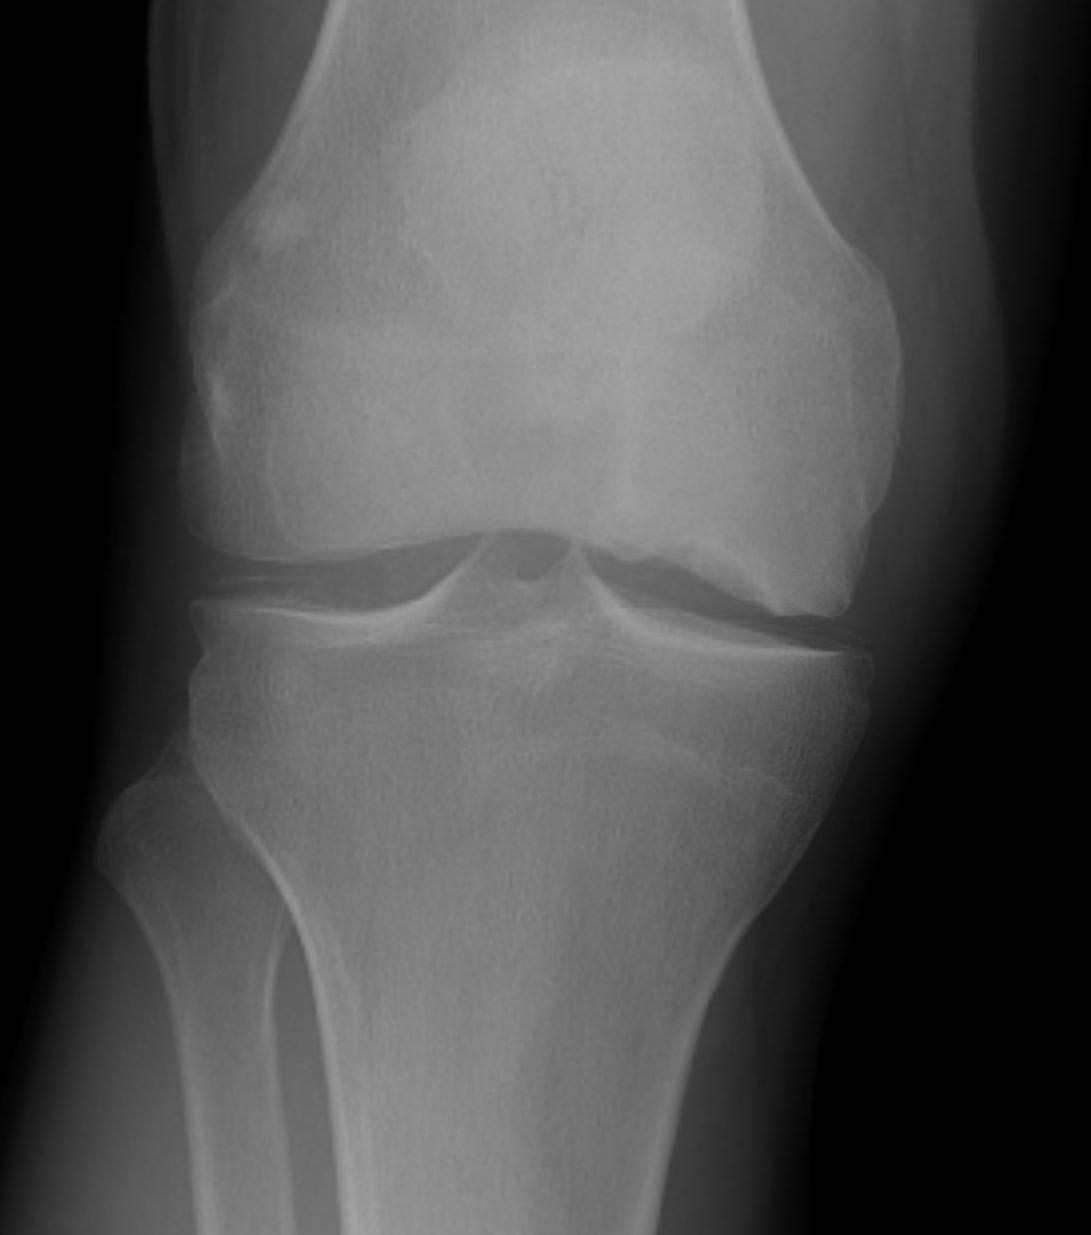

X-ray

Initially normal

Later develop

- subchondral lucent line / crescent Sign

- flattening of condyle

- patchy sclerosis

- can have rapid collapse into varus with development degenerative changes